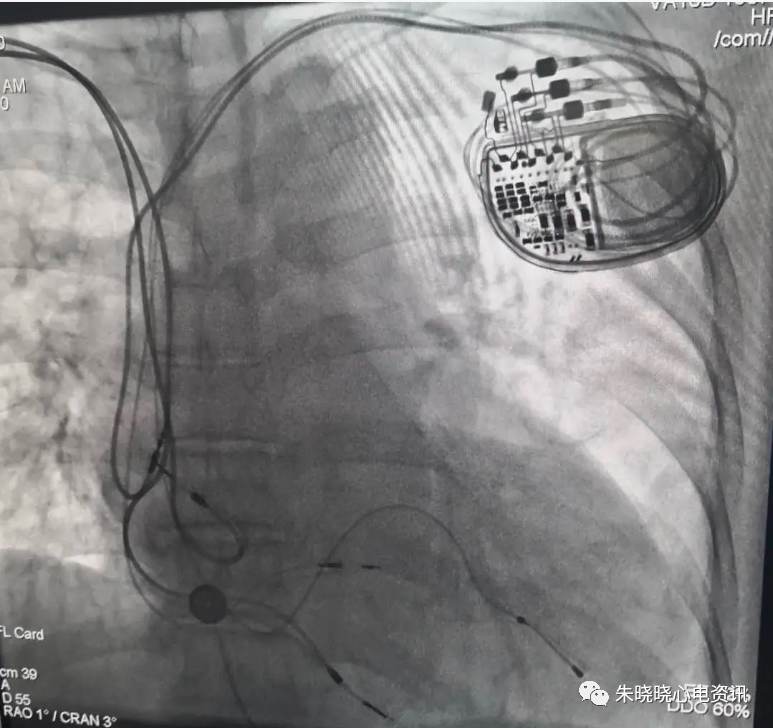

美敦力公司起搏器均为并列的圆型或菱形接线点(图14)

图14 左为美敦力起搏器,右为美敦力公司Vitatron起搏器